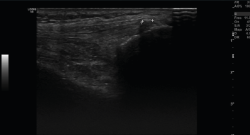

1. Ligamentos

Tanto el ligamento lateral interno (LLI) como el ligamento lateral externo (LLE) pueden ser valorados por ecografía (Figura 7).

Figura 7. Corte coronal de una ecografía de rodilla. A: engrosamiento del ligamento lateral externo en la inserción proximal por un esguince de grado I; B: engrosamiento del ligamento lateral interno.